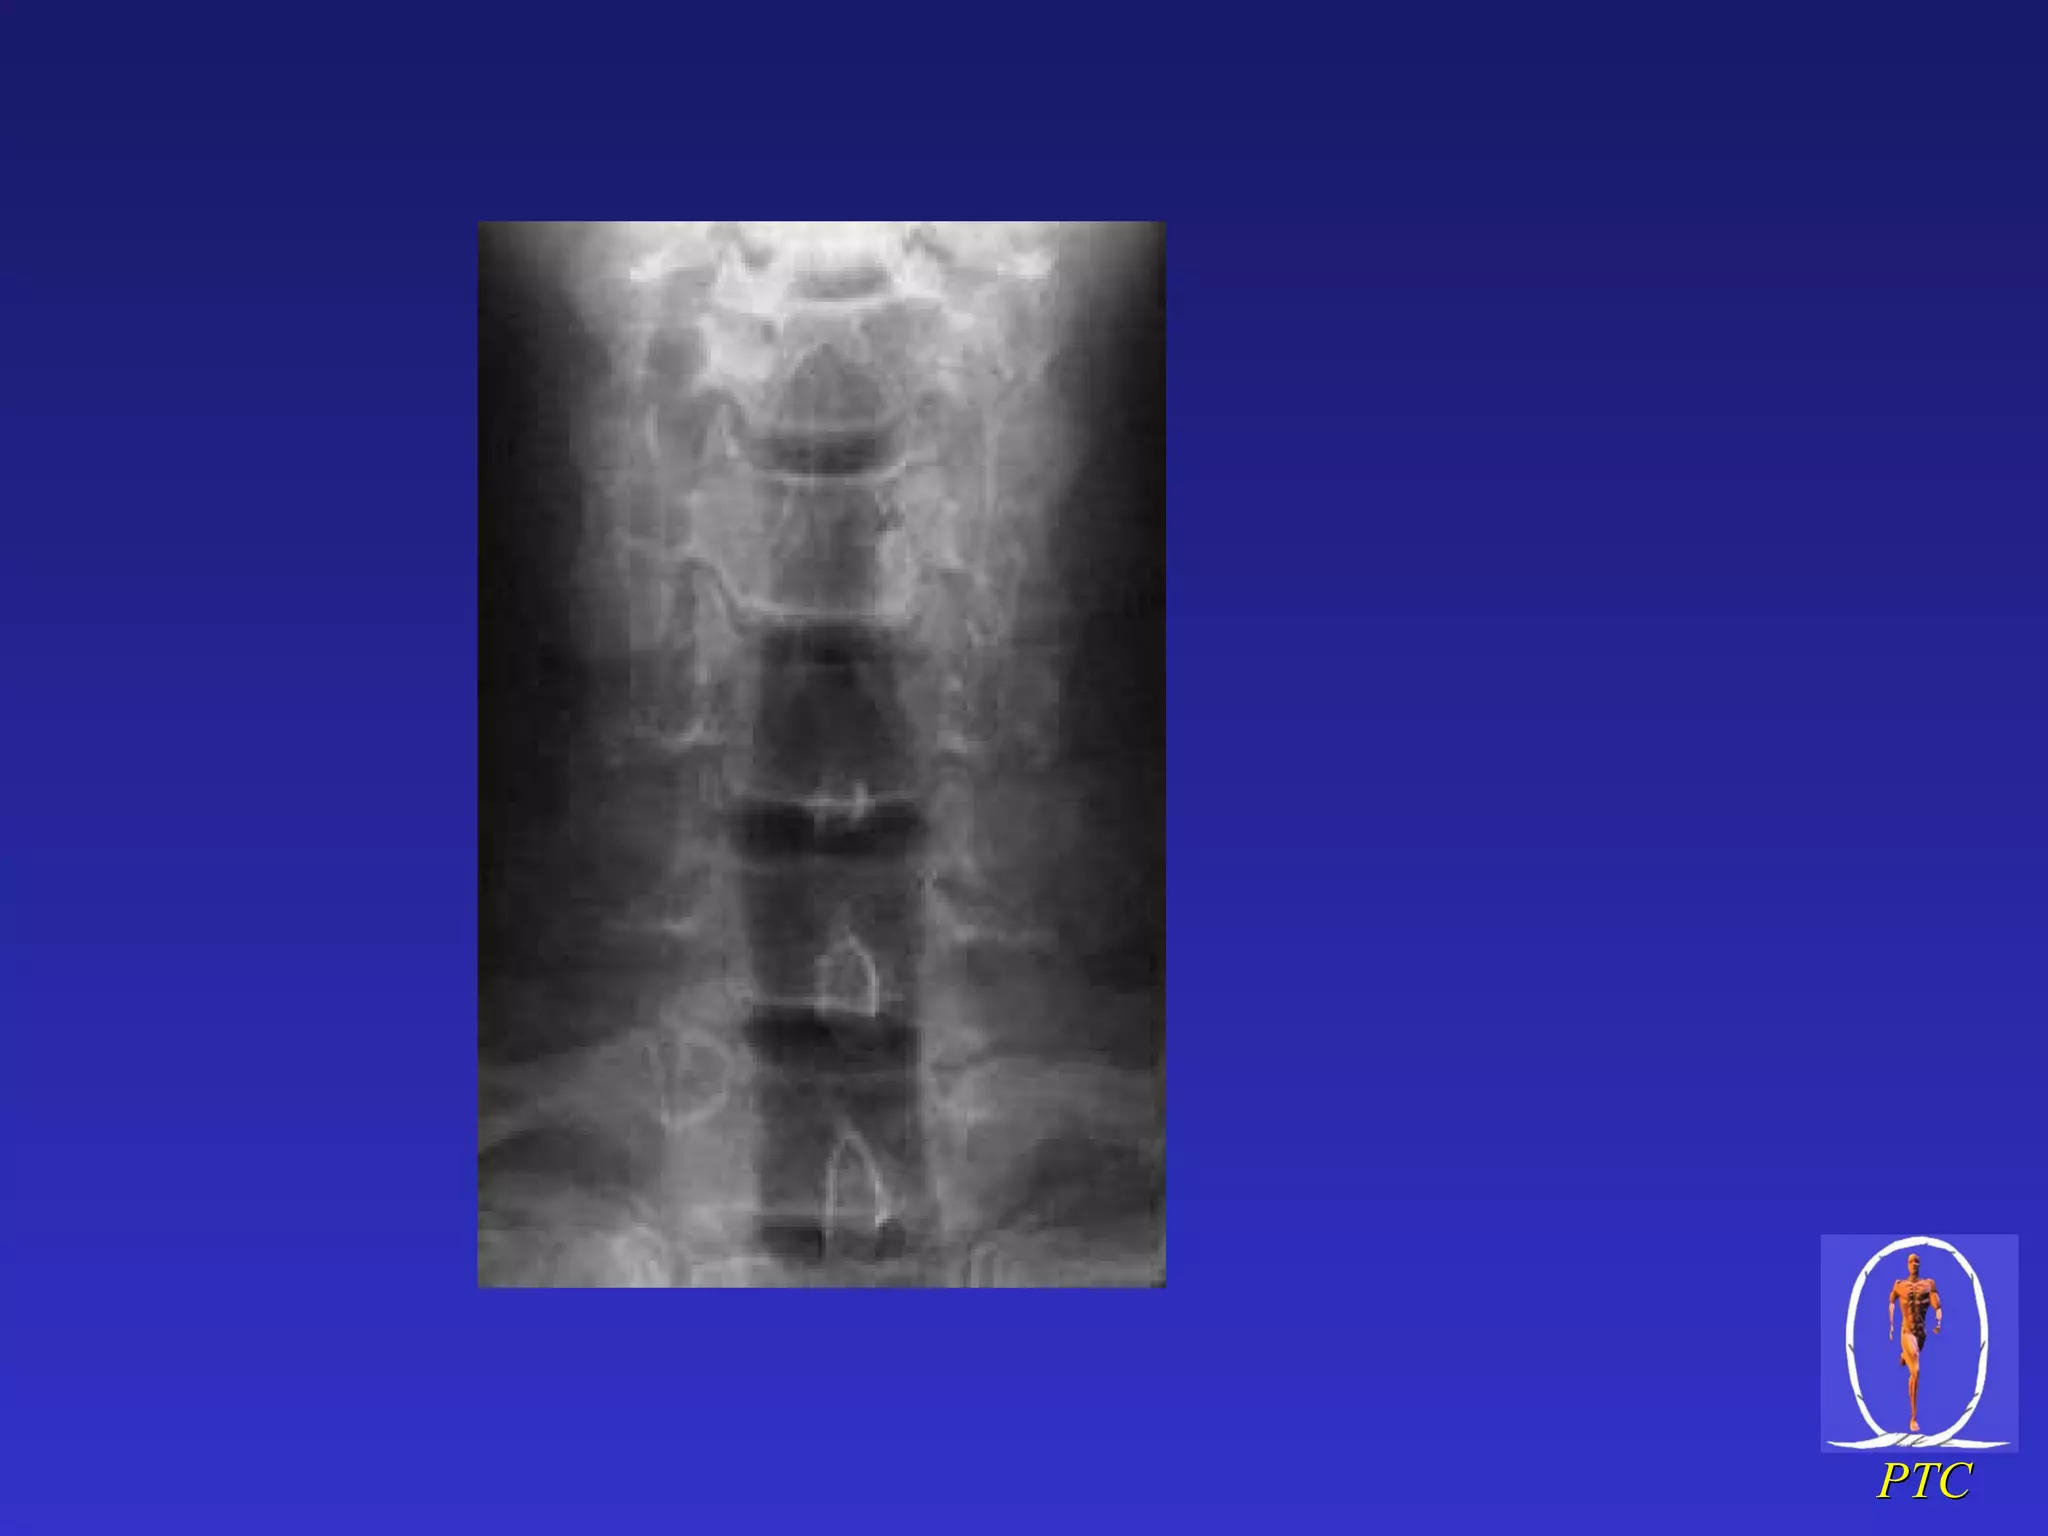

Open Mouth & AP Views Occipital condyle Lat mass C1 Lat mass C2 Odontoid Peg Bifid spinous process Unco-vertebral joint C7 T1

Open Mouth &AP Views Occipital condyle Lat mass C1 Lat mass C2 Odontoid Peg Bifid spinous process Unco-vertebral joint C7 T1